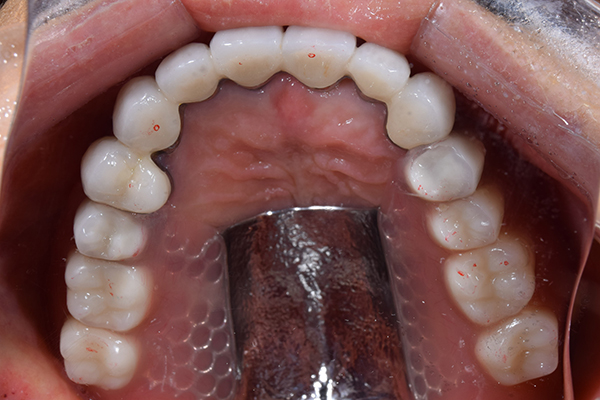

8.患者様のお口に入れて修正

この写真は、実際にお口の中にいれてみて、噛み合わせのチェックを行い、調整したものになります。 上下の入れ歯で青い点、赤い点がはっきりあり、これはしっかり奥歯で噛めるというサインになります。 また、入れ歯自体の大きさや、違和感が強くないか、お顔と調和しているか、唇との関係などをみていきます。もし、ここで大きな修正が発生する場合はもう一度お時間をもらって次回再度確認させて頂きます。 これで修正が終わったら、その模型を技工所に送り、入れ歯を完成させてもらいます。

9.完成

入れ歯が完成してきましたら、お口の中に入れていきます。 完成までに試適してきた時と同じように、見た目、お顔との調和、喋りやすさ、噛み合わせを見ていきます。入れ歯はレジン(プラスチック)が大半になりますので、どうしても作成時に重合収縮が起こります。 そのため、若干、試適時よりも、ずれが生じてしまいます。そのため、またしっかりフィットさせるために、咬合器という装置に入れ歯を付けてお口の外で噛み合わせの調整をしていきます。 そうすることで、しっかりした噛み合わせを再現することができます。 また、歯ぐき側は実際にお口の中に入れて痛みがある部分に関して、痛くないように調整します。 出来上がってきた入れ歯の調整を行います。 これでこの日はおしまいです。